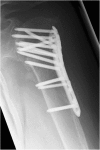

Locking nail versus locking plate for proximal humeral fracture fixation in an elderly population: a prospective randomised controlled trial

Background: Proximal humeral fractures (PHFs) are the third most common fracture in older patients. The purpose of the study was to prospectively evaluate the outcomes of PHF fixation with a locking blade nail (LBN) or locking plate (PHILOS) osteosynthesis in a homogeneous elderly patient population.

Methods: Inclusion criteria were an age > 60 years and the capacity to give informed consent. Patients with isolated tuberosity fractures, previous trauma or surgery, advanced osteoarthritis, fracture dislocation, pathological fractures, open fractures, neurological disorders, full-thickness rotator cuff tears, fracture line at the nail entry point or severely reduced bone quality intra-operatively were excluded. Eighty one patients with PHFs were randomised to treatment using LBN or PHILOS. Outcome measures comprised Constant score, age and gender adjusted Constant score, DASH score, VAS for pain, subjective overall condition of the shoulder (1-6) and active shoulder range-of-motion in flexion and abduction. Plain radiographs were obtained in two planes. All data were collected by an independent observer at 3, 6 and 12 months postoperatively.

Results: Thirteen patients were excluded intra-operatively due to rotator cuff tears, fracture morphology or poor bone-quality. Of the remaining 68 patients, 27 in the LBN and 28 in the PHILOS group completed the full follow-up. Mean age at surgery was 75.6 years and the majority of PHFs were three-part fractures (49 patients). Baseline demographics between groups were comparable. All outcome measures improved between assessments (p < 0.001). The LBN group showed improved DASH scores as compared to PHILOS at 12 months (p = 0.042) with fewer incidences of secondary loss of reduction and screw cut-out (p = 0.039). A total of 29 complications (in 23 patients) were recorded, 13 complications (in 12 patients) in the LBN group and 16 complications (in 11 patients) in the PHILOS group (p = 0.941). No significant inter-group difference was observed for any other outcome measures, nor was fracture morphology seen to be associated with clinical outcome or complication rate.

Conclusions: At short-term follow-up, LBN osteosynthesis yielded similar outcomes and complication rates to PHILOS plate fracture fixation in an elderly patient population, though with a significantly lower rate of secondary loss of reduction and screw cut-out.